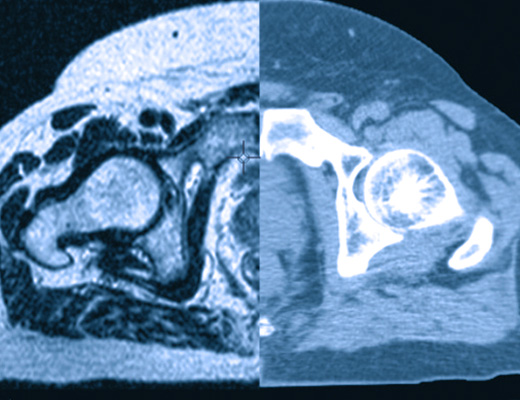

Para la planificacion este sistema permite la incorporacion de metodos complementarios de imagenes, siendo la base la Tomografia Axial. Estas imagenes pueden fusionarse con imagenes de Resonancia Magnetica y/o Tomografia por emision de positrones (PET), permitiendo al medico pasar de un conjunto a otro de imagenes de manera continua para seleccionar la mejor visualizacion tanto del blanco como de otras estructuras de interes.